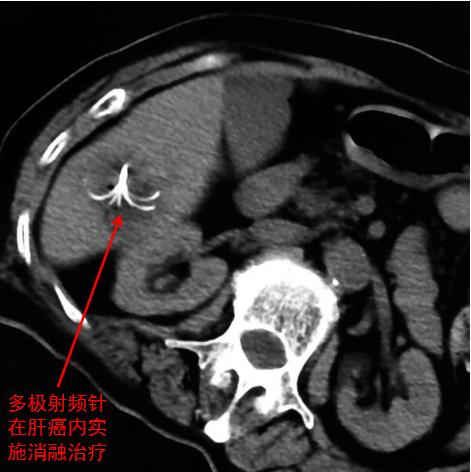

肝癌射频消融治疗

因为,介入有多种不同的方式,如局部灌注、栓塞化疗、射频消融、微波消融、冷冻、无水酒精消融、化疗药盒植入、放射粒子植入等方式方法针对肿瘤本身,也还有引流、支架植入等方式来处理并发症。